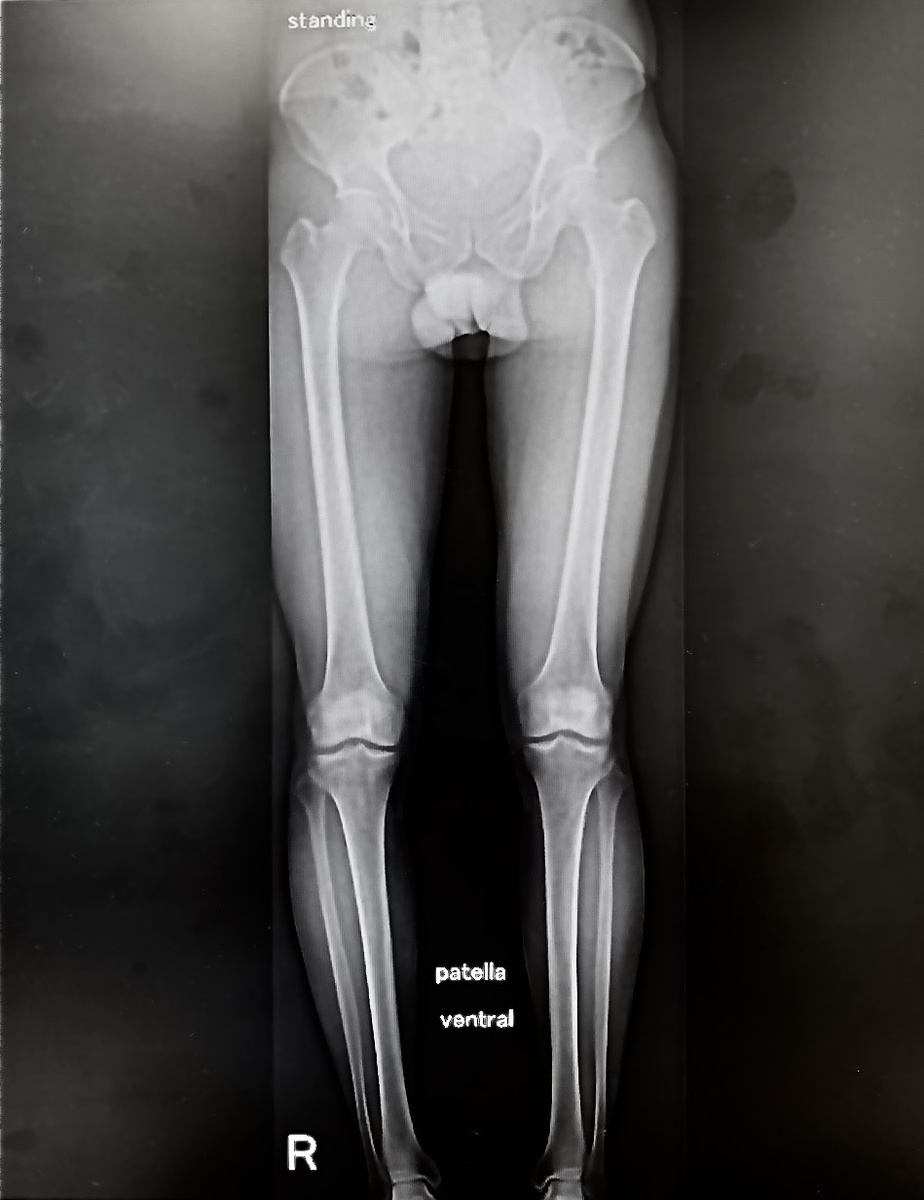

Казалось бы - нонсенс, как можно порвать мениск в бассейне? Но - нет, не всё так однозначно. Посмотрел коллега - да, оторванную часть мениска нужно удалять. Направил пациента ко мне, ибо заметил (молодец) вальгус правой стопы. Оцениваю походку пациента, невооруженным глазом вижу варусную (О-образную) деформацию правой ноги. Делаем рентгеновскую сшивку:

Возможно, кто-то зоркий и сам заметит деформацию правой ноги относительно механической оси, для остальных - следующий рисунок:

Слева ось отличная, справа коленный сустав почти весь находится кнаружи от оси, а это означает перегрузку внутреннего отдела колена. Именно там и порвался мениск! Он годами был перегружен, накапливались дегенеративные изменения, и, стоило перегрузить ногу ПЛАВАНИЕМ, как мениск порвался. Следом будет разрушаться хрящ (уже разрушается, кстати), то есть - артроз. Если так дальше пойдёт, на горизонте одномыщелковое протезирование.

Идём выше. Изогнутая нога - укороченная нога. Укорочение ноги - перекос таза, неизбежно:

А где перекос таза, там и перекос/деформация позвоночника. Чистая механика, причём, если захваченный на этой плёнке кусочек наклонен вправо, то выше, поверьте, позвоночник компенсаторно наклонен влево. Компенсаторно, для баланса.